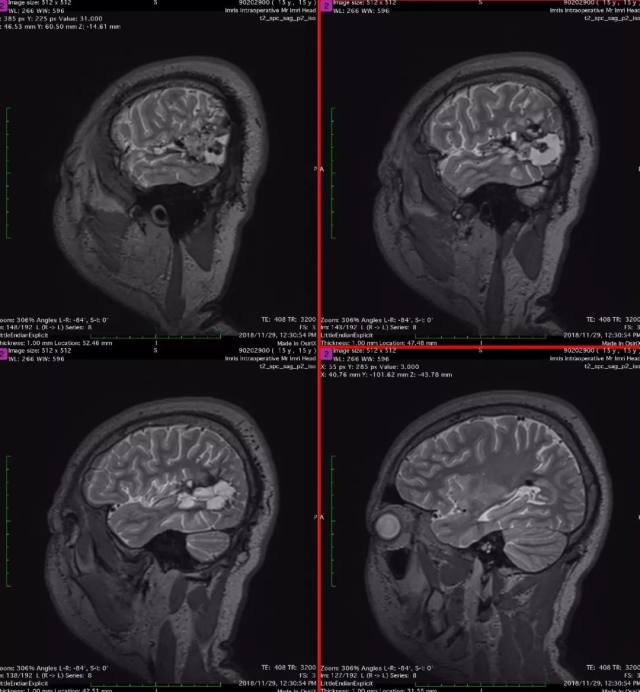

2、术前影像资料

图 3 术前 T2 矢状位:左颞顶枕血管畸形术后;混杂信号;考虑畸形残余伴出血。